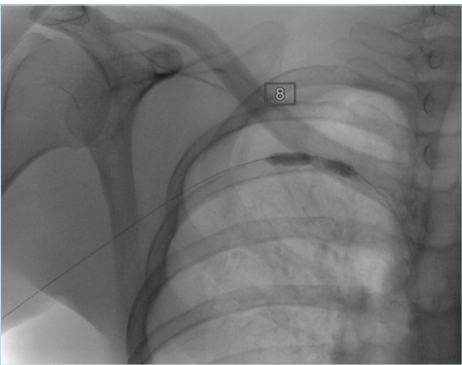

Plain radiography

Plain radiography is used adjunctively to detect cervical ribs, elongated C7 transverse processes, or posttraumatic bone healing that may alter thoracic outlet anatomy. It is not definitive but is often a useful first step (Figure 7).

Figure 7. X-ray with elongated transverse process (right image) and complete cervical rib (left image).